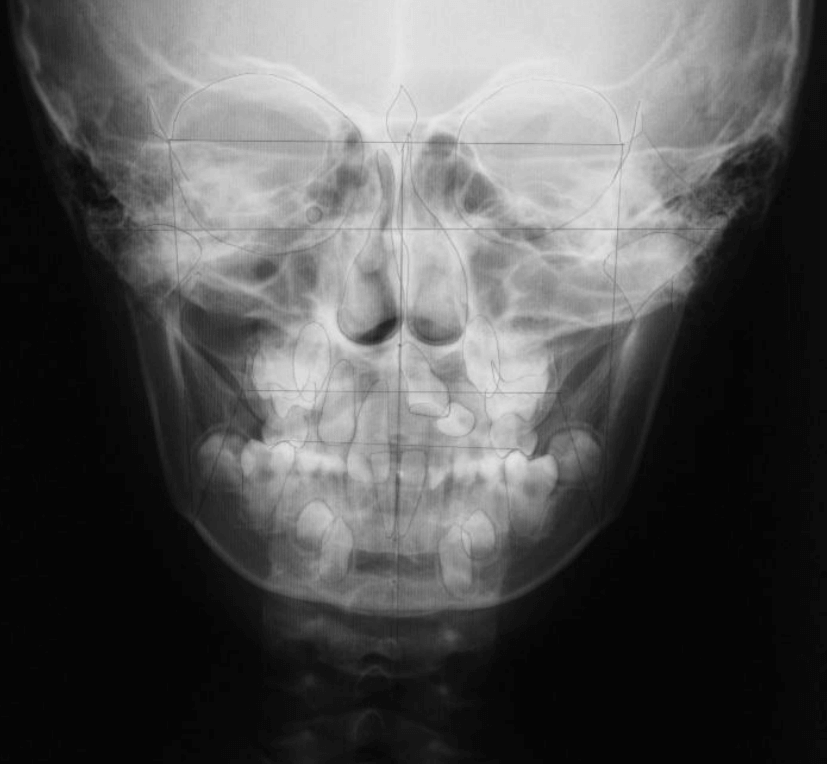

| 年齢・性別 | 8歳3ヶ月の男児 |

|---|---|

| 主訴 | 上顎前歯の位置異常に不安を抱え、歯並びと将来的な咬合状態を整える目的で来院された患者様です。 特に左側の前歯(中切歯および側切歯)の萌出が確認できないことがきっかけとなりました。 |

| 治療期間・回数 | 約5年10ヶ月 |

| 費用 | 460,000円(税別) |